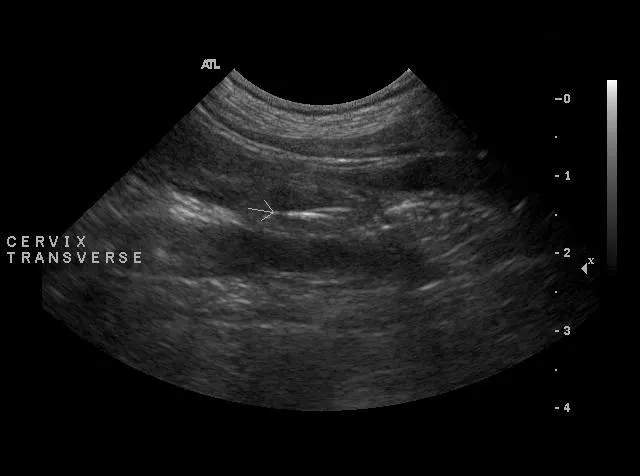

Vaginal cytology (Figure 2B) revealed moderate numbers of parabasal cells and numerous neutrophils. Abdominal ultrasonography showed a hyperechoic linear object within the uterine stump, dorsal to the urinary bladder (Figure 2C). Examination findings and vaginal cytology failed to support hormonal influence (no vulvar swelling or cornification).

Vaginoscopy (Figure 2D) exposed a foxtail (grass awn) embedded in the vaginal os of the cervix. It was removed with retrieval forceps under endoscopic guidance.